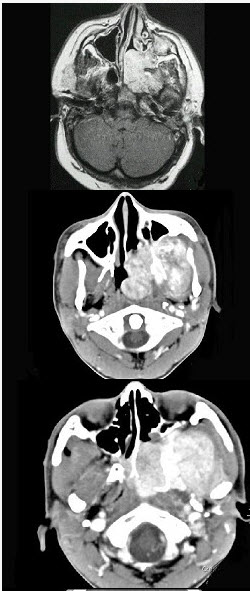

男性,19岁,左侧鼻腔反复出血一年余,CT、MRI扫描如图所示,请选择最可能诊断()。

A . 鼻息肉

B . 鼻咽腔脓肿

C . 鼻咽部青年纤维血管瘤

D . 鼻咽癌

E . 鼻咽部淋巴瘤

男性,19岁,左侧鼻腔反复出血1年余,CT、MRI扫描如图所示,请选择最可能诊断

[单选题]男性,19岁,左侧鼻腔反复出血1年余,CT、MRI扫描如图所示,请选择最可能诊断()A .鼻息肉B .鼻咽腔脓肿C .鼻咽部青年纤维血管瘤D .鼻咽癌E .鼻咽部淋巴瘤

男,19岁,左侧鼻腔反复出血1年余, CT、MRI扫描如图,最可能的诊断是

[单选题]男,19岁,左侧鼻腔反复出血1年余, CT、MRI扫描如图,最可能的诊断是A.鼻息肉B.鼻咽腔脓肿C.鼻咽部青年纤维血管瘤D.鼻咽癌E.鼻咽部淋巴瘤

男,19岁,左侧鼻腔反复出血1年余,CT、MRI扫描如图,最可能的诊断是()

[单选题]男,19岁,左侧鼻腔反复出血1年余,CT、MRI扫描如图,最可能的诊断是()A . 鼻息肉B . 鼻咽腔脓肿C . 鼻咽部青年纤维血管瘤D . 鼻咽癌E . 鼻咽部淋巴瘤